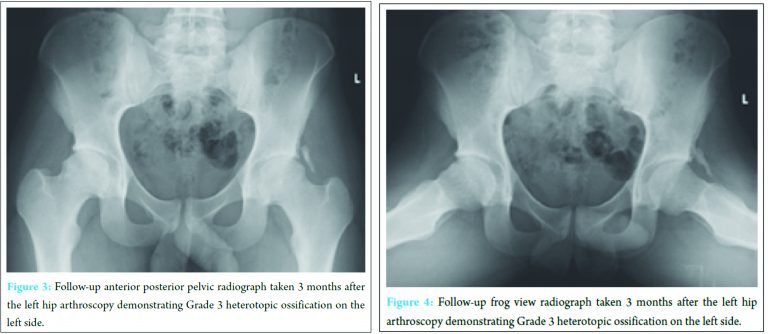

Intraoperative findings included chondral detachment at the chondrolabral junction in zone 3 and an adjacent partial labral tear. These were treated with chondroplasty, microfracture, acetabular osteoplasty and labral repair followed by osteoplasty of the femoral head-neck junction. No HO prophylaxis was given. Follow-up radiographs at 3 months after the left hip arthroscopy showed Grade 3 HO on the left side (Fig. 3 and 4). On the 2nd post-operative visit (following 6 weeks of non-weight bearing rehabilitation) the patient complained of contralateral (right-sided) hip pain.